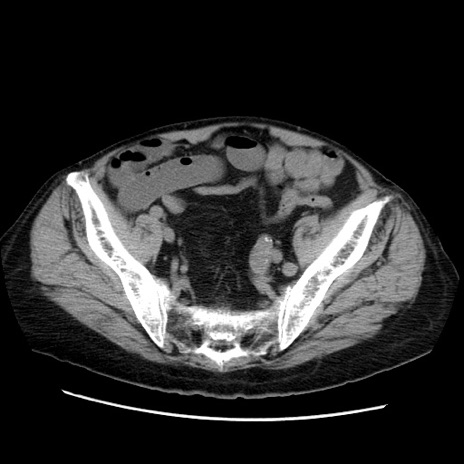

冠状断像